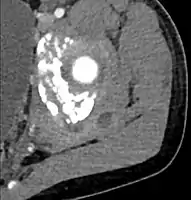

CT with IV contrast showing enlargement and heterogeneous hypodensity in the right pectoralis major muscle. A focal abscess collection with gas within it is present medially. There are enlarged axillary lymph nodes and some extension into the right hemithorax. Note the soft tissue and phlegmon surrounding the right internal mammary artery and vein. The patient was HIV+ and the pyomyositis is believed to be due to direct inoculation of the muscle related to parenteral drug abuse. The patient admitted to being a "pocket shooter"

CT with IV contrast showing enlargement and heterogeneous hypodensity in the right pectoralis major muscle. A focal abscess collection with gas within it is present medially. There are enlarged axillary lymph nodes and some extension into the right hemithorax. Note the soft tissue and phlegmon surrounding the right internal mammary artery and vein. The patient was HIV+ and the pyomyositis is believed to be due to direct inoculation of the muscle related to parenteral drug abuse. The patient admitted to being a "pocket shooter" CT exam showing a multiloculated fluid collection in the left gluteus minimus muscle found to be a staph aureus pyomyositis in a 12-year-old healthy boy.